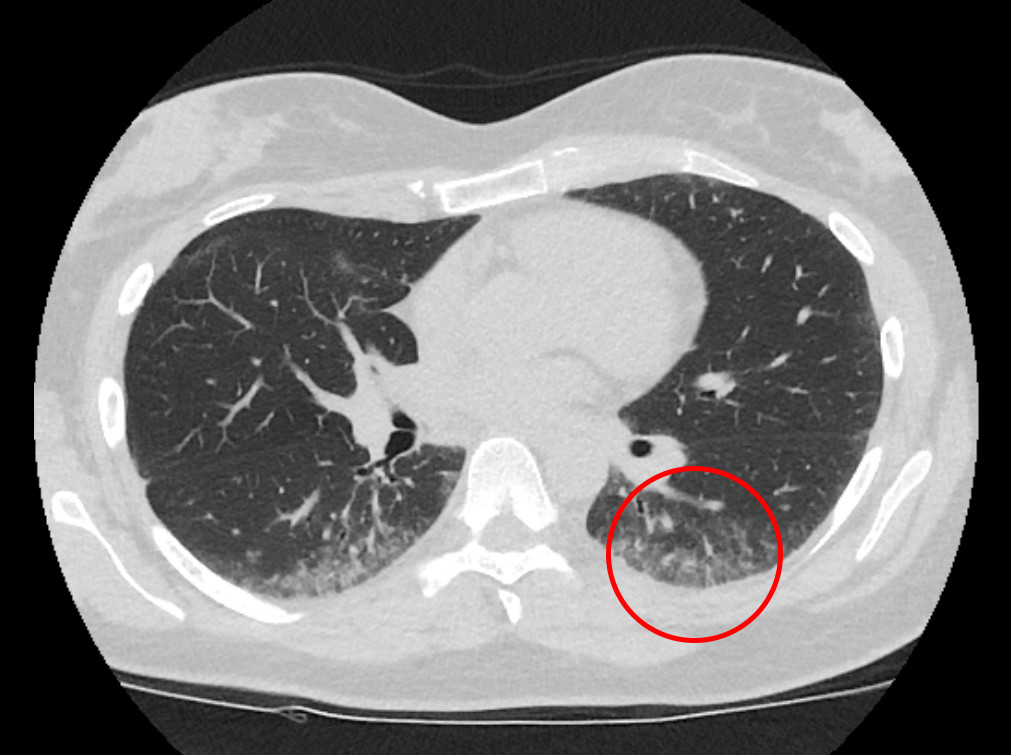

Two weeks later she was assessed at the Department of Pulmonary Medicine. She was found on examination to have unobstructed respiration at rest. Spirometry confirmed decreased FVC 2.1 l (52 %), FEV1 2.0 l (54 %) and slightly increased FEV1/ FVC 0.9. Measurement of gas diffusion showed reduced carbon monoxide diffusion capacity (DLCO) 4.7 SI (46 %). Body plethysmography demonstrated severely reduced total lung capacity of 3.1 l (58 %). During a six-minute walk test, oxygen saturation fell from 98 % to 79 %. A lung CT revealed peripheral coarse reticular markings that aroused suspicion of non-specific interstitial pneumonia (NSIP) of the fibrotic type (Fig. 1). Echocardiography revealed normal heart valves and pressures and an ejection fraction of 55 %. A 24-hour ECG and 5-day ECG monitoring revealed no signs of arrhythmia. Blood tests showed haemoglobin 12.9 g/dl (11.7–15.3), sedimentation rate 26 mm (1–17). C-reactive protein, thrombocytes and leukocytes were within the respective reference ranges. Alanine amino transferase (ALT) was 54 U/l (10–45 U/l), alkaline phosphatase (ALP) 52 U/l (35–105) and lactate dehydrogenase (LD) 310 (105–205 U/l). She tested negative for rheumatoid factor (RF), anti-cyclic citrullinated peptide (anti-CCP) and anti-neutrophil cytoplasmic antibody (ANCA). Anti-nuclear antibodies (ANA) were weakly positive, but with negative subgroups.

Figure 1 High-resolution thoracic CT shows peripheral subpleural micronodular lung opacities with some ground glass opacities.

High resolution CT (HRCT) of the thorax showed unchanged subpleural micronodules with some ground glass opacities in both lungs, most pronounced in the lower lobes. Based on these findings sarcoidosis and hypersensitivity pneumonitis were suggested as possible differential diagnoses of non-specific interstitial pneumonia. On suspicion of myositis, magnetic resonance imaging (MRI) of the hip and thigh was carried out two days after hospitalisation. It revealed normal muscle tissue with no evidence of myositis, but with multiple enlarged lymph nodes in the left inguinal area and pelvis along the external iliac artery and vein.